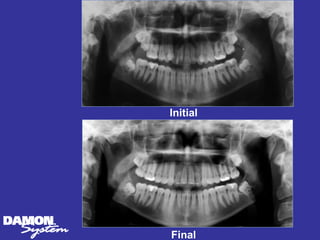

Upper CT scans7 mos in retention Note presence of bone on buccal and lingual sides of roots Upper first molars width change 9 mm

Upper CT scans7 mos posttreatment Upper 2nd bicuspids width change 11 mm

Upper CT scans7 mos posttreatment Upper 1st bicuspids width change 12 mm

Change: Cuspids 2mm, 1st Bicuspids 12 mm, 2nd Bicuspids 11 mm, Molars 9 mm